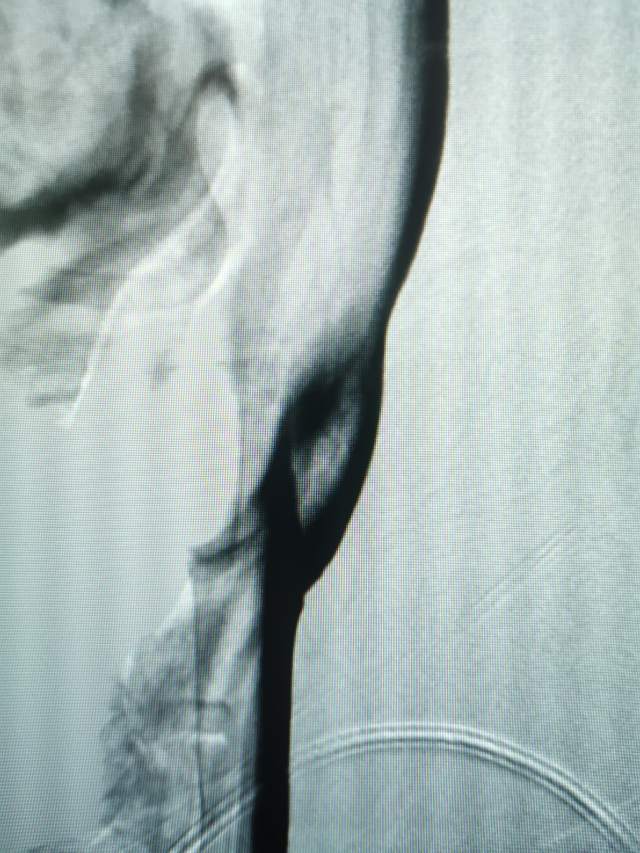

左侧颈内动脉蹼(起始部) 左侧颈内动脉蹼(起始部)的紊乱血流动力学

左侧颈内动脉蹼(起始部)的紊乱血流动力学 左侧颈内动脉蹼(起始部)的紊乱血流动力学